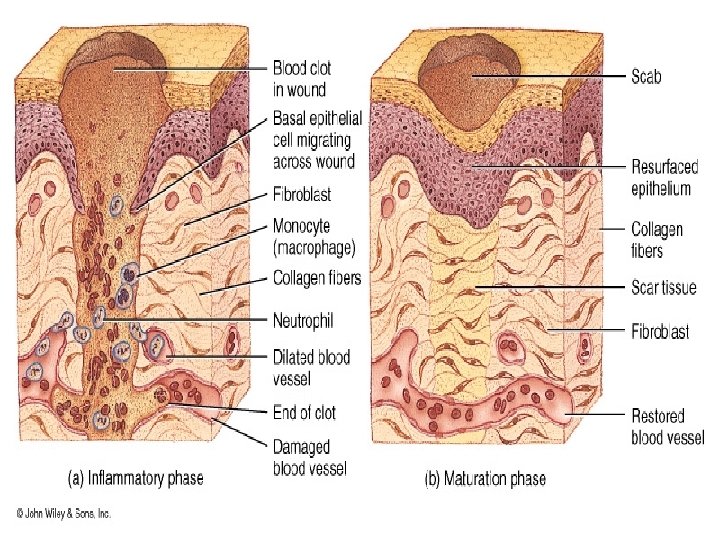

Deep Wound Healing • When an injury extends to tissues deep to the epidermis, the repair process is more complex than epidermal healing, and scar formation results. • Healing occurs in 4 phases – inflammatory phase has clot unite wound edges and WBCs arrive from dilated and more permeable blood vessels – migratory phase begins the regrowth of epithelial cells and the formation of scar tissue by the fibroblasts – proliferative phase is a completion of tissue formation – maturation phase sees the scab fall off • Scar formation – hypertrophic scar remains within the boundaries of the original wound – keloid scar extends into previously normal tissue • collagen fibers are very dense and fewer blood vessels are present so the tissue is lighter in color

Four Phases of Deep Wound Healing 1. Inflammatory stage: a. Blood clot forms b. Inflammation is the result of vasodilation which helps deliver WBC’s to help eliminate microbes

Four Phases of Deep Wound Healing 2. Migratory Phase: a. Clot becomes a scab b. Epithelial cells migrate beneath scab to repair epithelium c. Fibroblast migrate into the area to repair connective tissue d. New tissue is called granulation tissue

Four Phases of Deep Wound Healing 3. Proliferative phase: a. Extensive growth of epithelial cells b. Deposition of collagen fibers by fibroblasts c. Continued growth of vascular network 4. Maturation phase: a. Scab sloughs off b. Collagen fibers become more organized c. Fibroblasts decrease in number